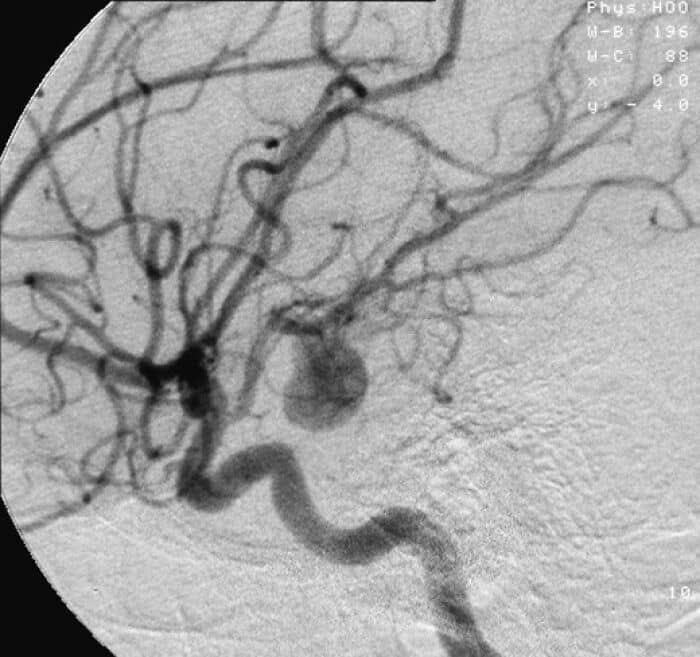

#7

Sudden aneurysms are pretty scary.

PapaTua:

My sister passed away this way right in front of me.

She had a mild headache all day, then a sharper pain for about 30 seconds, and then gone.

I’ll be the same age she was when she passed in a year or two. I hope to go the same way at the same age.